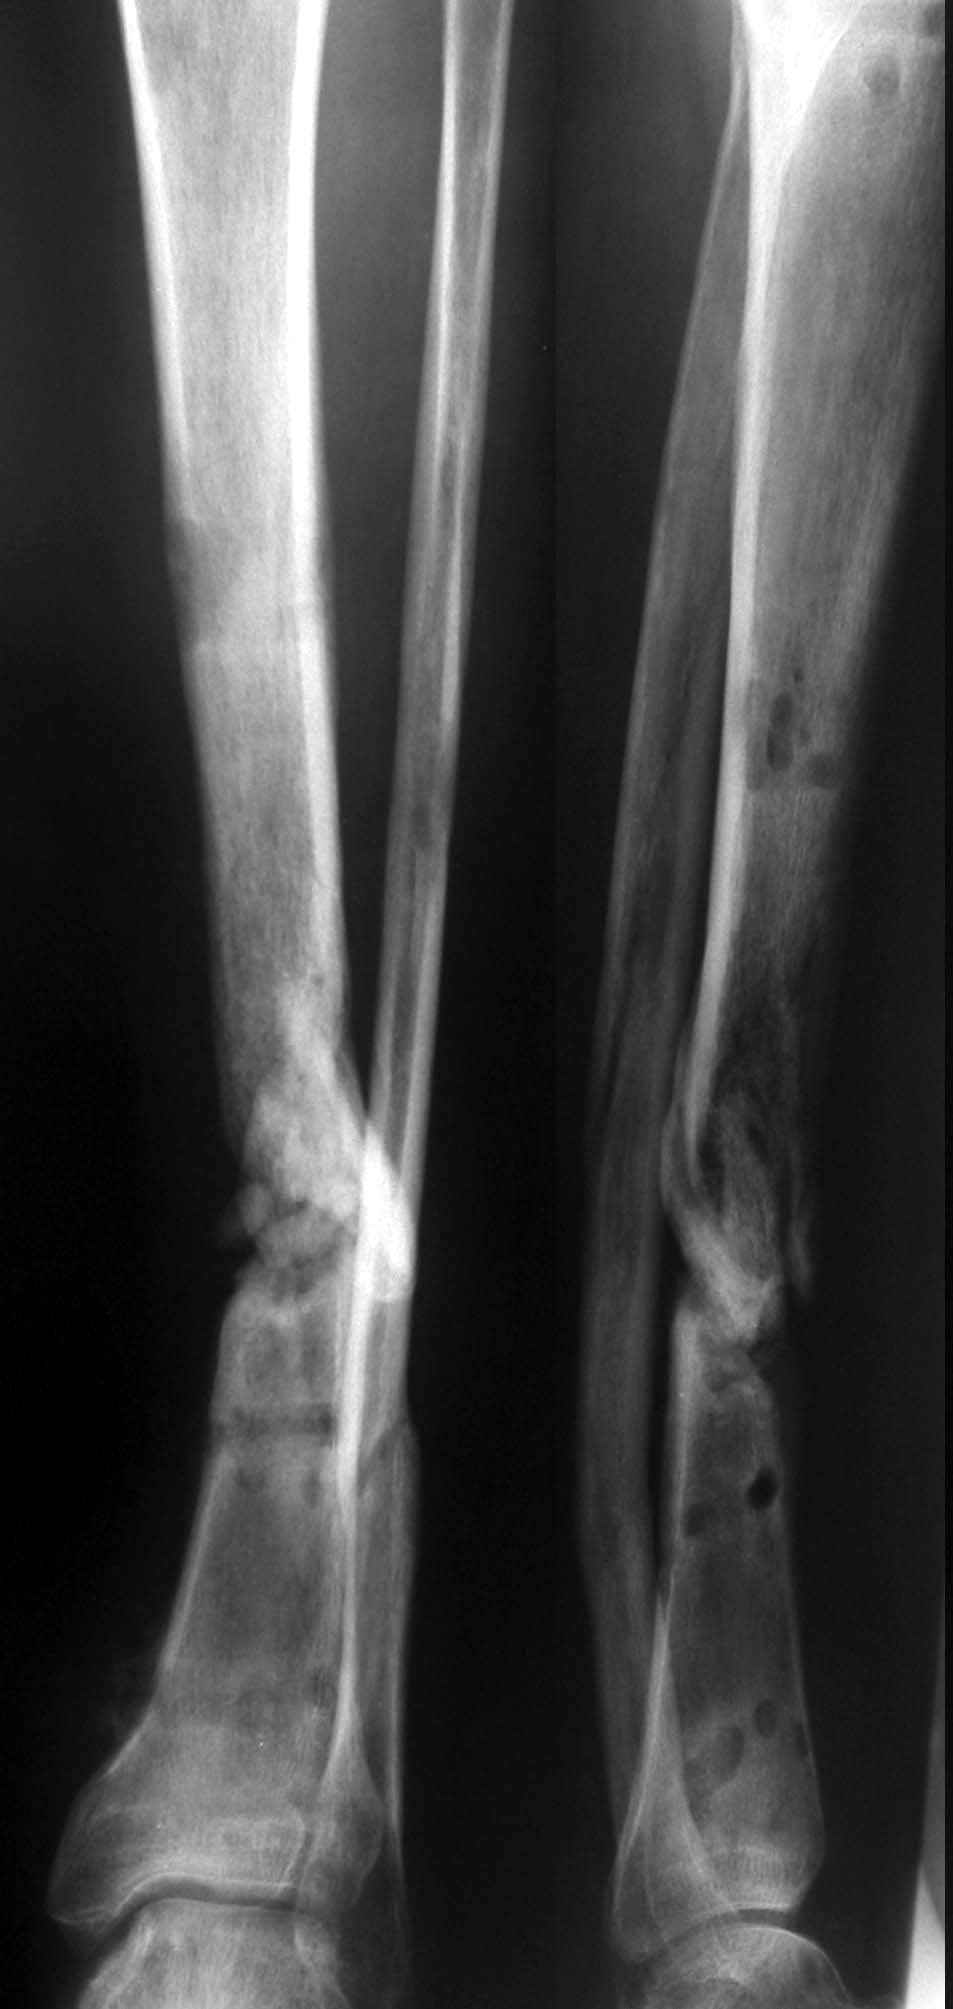

Несросшийся перелом голени

больной переведён из другого лечебного учреждения, травма высокоэнергетическая на производстве, 10мес. лечился в АВФ по поводу открытого перелома костей левой голени, течение осложнилось спицевым остеомиелитом, аппарат мы демонтировали, провели секвестрнекрэктомию, раны зажили, свищей нет.

Планирую через 6-8недель стеосинтез блокированным штифтом без рассверливания,периостальную декортикацию Хотелось бы услышать советы по тактике лечения этого больного.

Атрофический (болтающийся) пседартроз - это когда две удаленных друг от друга сосульки, с хорошими замыкательными пластинками. Тут еще была бы оправдана открытая обработка концов. А как Вы сами пишете, подвижность тугая, а по снимку есть неплохие контактирующие участки.

Во-первых в области стыка недостаточна площадь контакта костных отломков.

Во-вторых сопостовляемые поверхности неконгруентны.

В-третьих остеосинтез штифтом в сочетании с остеотомией малоберцовой кости, в данном случае, приведет к укорочению.

В-четвертых высок риск обострения остеомиелита т.к. мало времени после его купирования.